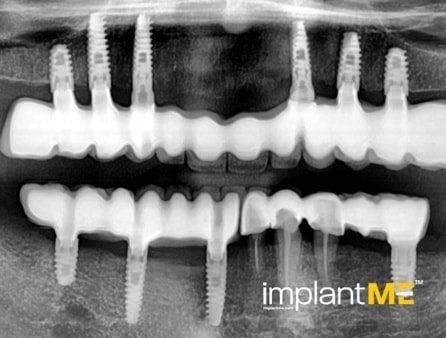

Τα ελκυστικά και ιδιαίτερα υγιή δόντια δεν είναι μόνο καθοριστικό μέρος της εμφάνισής μας, αλλά και της προσωπικότητάς μας. Παλαιότερα, η απώλεια ενός ή περισσοτέρων δοντιών είχε καθοριστικό αντίκτυπο στον τρόπο εμφάνισης των ανθρώπων. Λόγω της σύγχρονης στοματικής εμφυτευματολογίας, αυτό δεν συμβαίνει πλέον. Με συγκριτικά μικρές χειρουργικές επεμβάσεις από το στόμα, μεμονωμένα ή όλα τα ελλείποντα δόντια μπορούν να αντικατασταθούν από εμφυτεύματα, αισθητικά και λειτουργικά ίσα με τα φυσικά δόντια. Μέσω της εισαγωγής εμφυτευμάτων που σχηματίζονται σε ρίζα, είναι δυνατόν να αποφευχθούν αλλοιώσεις των γειτονικών δοντιών και να αγκυρωθούν στεφάνες που δύσκολα διακρίνονται από τα πραγματικά δόντια στα κενά των δοντιών. Οι στεφάνες ή οι γέφυρες που υποστηρίζονται από εμφύτευμα στερεώνονται στα εμφυτεύματα που είναι αγκυροβολημένα στο οστό, γεγονός που δίνει στους ασθενείς μια αίσθηση μάσησης σχεδόν διακριτή από τα δόντια τους. Σε περίπτωση πλήρους έλλειψης δοντιών, τα εμφυτεύματα μπορούν να παρέχουν αξιόπιστες αγκυρώσεις για αφαιρούμενα προσθετικά καθώς και για μεγάλες σταθερές γέφυρες.

Τα οδοντικά προσθετικά που υποστηρίζονται από εμφύτευμα βρίσκονται όσο πιο κοντά μπορείτε να φτάσετε στα φυσικά δόντια. Τα στεφάνια των εμφυτευμάτων βαθμολογούνται με τη φυσική τους εμφάνιση, τα εμφυτεύματα με τη σταθερότητα τους και και τα δύο με τη θετική τους επίδραση στη λειτουργική συντήρηση ολόκληρης της μαστιχικής συσκευής.